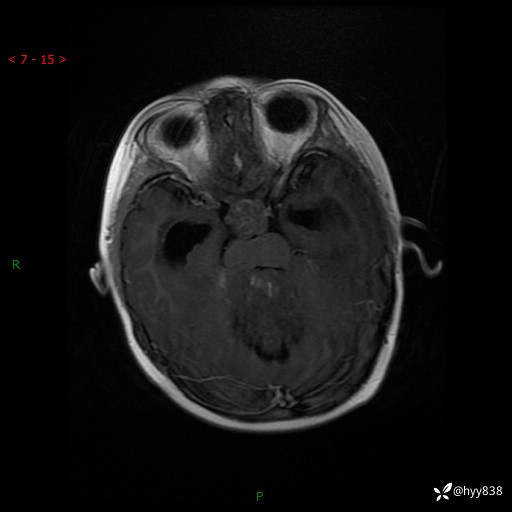

性别:女

年龄:3岁

简要病史:发现行走不稳2个月,加重1个月

颅脑MRI平扫+增强

三脑室、四脑室多发病变,如何分析?

髓母细胞瘤 (13)